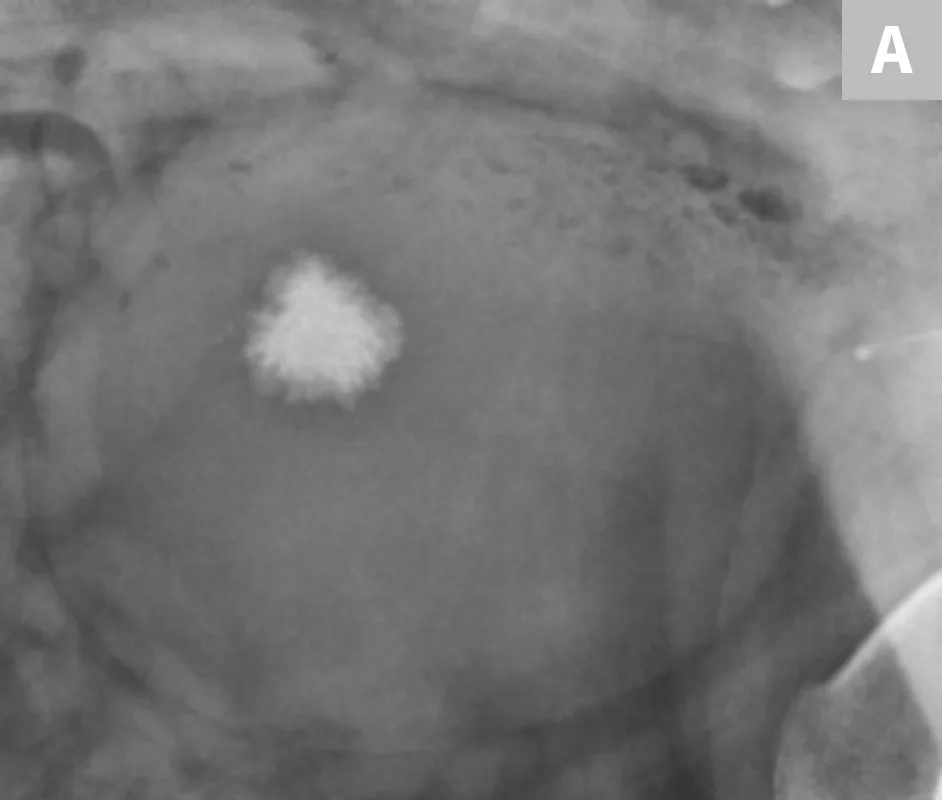

Renal calculi can vary markedly in size, number, shape, and opacity (Figure 3). Dystrophic mineralization of the renal parenchyma, often associated with the collecting system, is another differential for mineralization localized to the kidney (Figure 4). A combination of radiography, positive contrast radiography (excretory urography), and ultrasonography has been shown to have an increased sensitivity for the diagnosis of ureteral calculi when compared with ultrasonography alone (Figure 5).4

FIGURE 4A

1 / 2

Close-up radiograph of the left kidney in a dog with well-defined, linear regions of mineralization localized to renal diverticula.